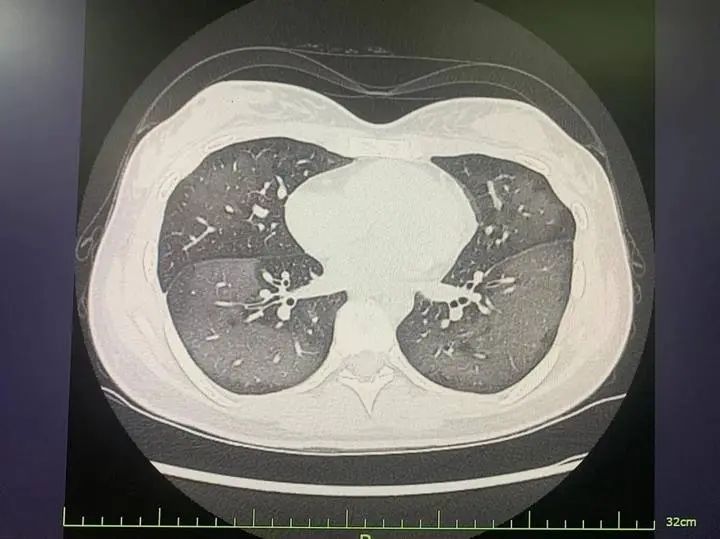

临床症状判断新型肺炎的常见症状包括:呼吸道症状:以干咳为主,可能伴随少量痰液,严重者出现胸闷、气喘,甚至呼吸困难。全身症状:发热(多为中低热,少数患者无发热)、乏力、肌肉酸痛,部分患者可能感到极度疲惫。

症状表现普通发热以发热、咳嗽、喉咙痛、头痛、肌肉疼痛为主,症状通常较轻且在数日内自行缓解。新型肺炎除上述症状外,还可能伴随呼吸困难、胸痛、乏力、腹泻,严重者可能发展为呼吸衰竭甚至死亡。呼吸困难是新型肺炎的典型警示信号,需高度警惕。

1、症状差异普通发烧以发热、寒战、头痛、肌肉疼痛为主,常伴咳嗽、流涕、喉咙痛等上呼吸道感染症状,整体症状相对局限。新型肺炎除发热、咳嗽外,更易出现乏力、呼吸困难,少数患者可能伴腹泻、呕吐等消化系统症状,且呼吸系统症状进展更快。

3、症状表现普通发热以发热、咳嗽、喉咙痛、头痛、肌肉疼痛为主,症状通常较轻且在数日内自行缓解。新型肺炎除上述症状外,还可能伴随呼吸困难、胸痛、乏力、腹泻,严重者可能发展为呼吸衰竭甚至死亡。呼吸困难是新型肺炎的典型警示信号,需高度警惕。